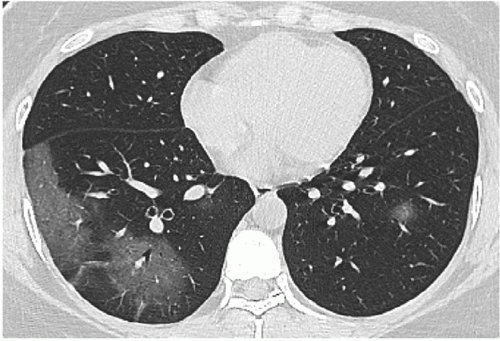

Pulmonary Ct Manifestations Of Covid 19 Changes Within 2 Weeks Duration From Presentation Egyptian Journal Of Radiology And Nuclear Medicine Full Text

ejrnm.springeropen.com